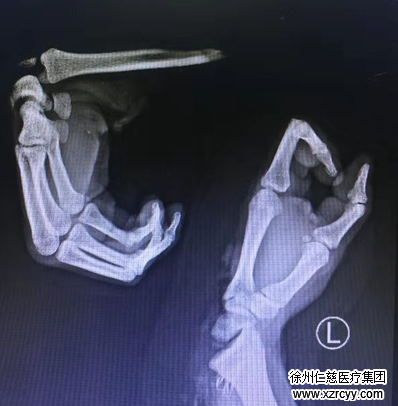

术中探查发现,患者左前臂尺侧中段至左手第3掌指关节斜行完全离断,左尺骨骨折,左桡骨远端关节面骨折,舟状骨、大多角骨等多处骨折,腕关节脱位,韧带破裂,多处血管断裂……